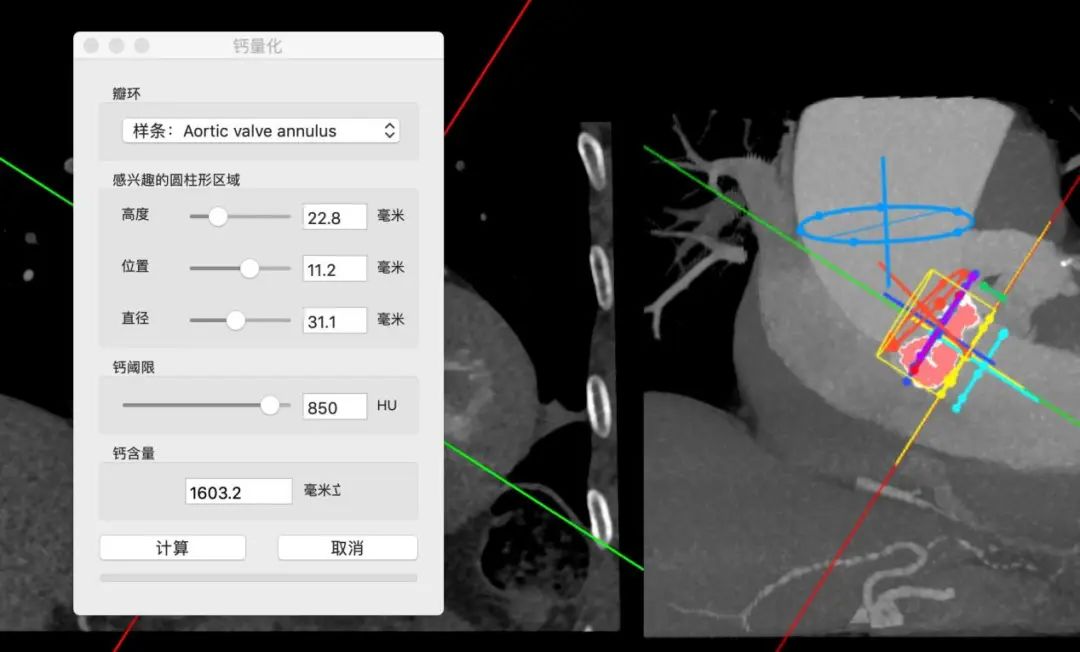

瓣环85.7mm,平均径26.7mm,LOT周长88.5mm,平均径27.5mm,瓣叶L-R融合,瓣叶重度钙化,钙化主要分布于右瓣叶、无冠瓣和左右瓣叶融合脊,瓣上4/6mm,预计推开空间周长84.5mm。

第二例病人同样为高难度病例,Type1型L-R融合二叶瓣,钙化积分1300,瓣叶增厚、轻度钙化,钙化分布于瓣叶及左右瓣叶融合脊。

瓣环周长87.4mm,平均径27.1mm。LVOT周长90.5mm,平均径28.5mm。

瓣上4mm/6mm,预估可推开空间周长81.8mm/75.8mm。